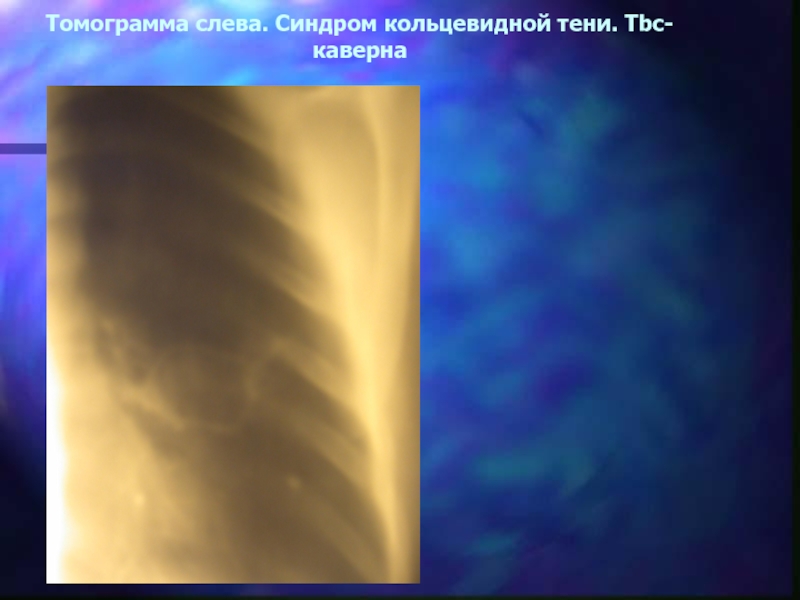

Рентгенологические изображения и синдромы патологии легких

Раздел: Кадры-подсказки